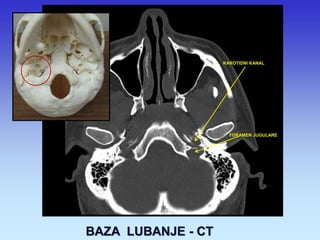

BAZA LUBANJE - CT

KAROTIDNI KANAL

FORAMEN JUGULARE